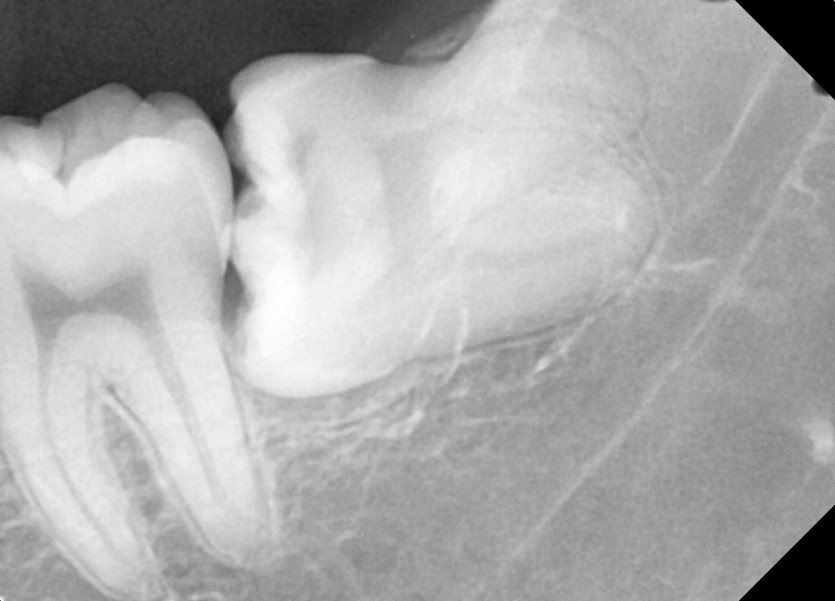

#28,38 사랑니 발치

구강 외과 전문의가 당일 발치하였습니다.